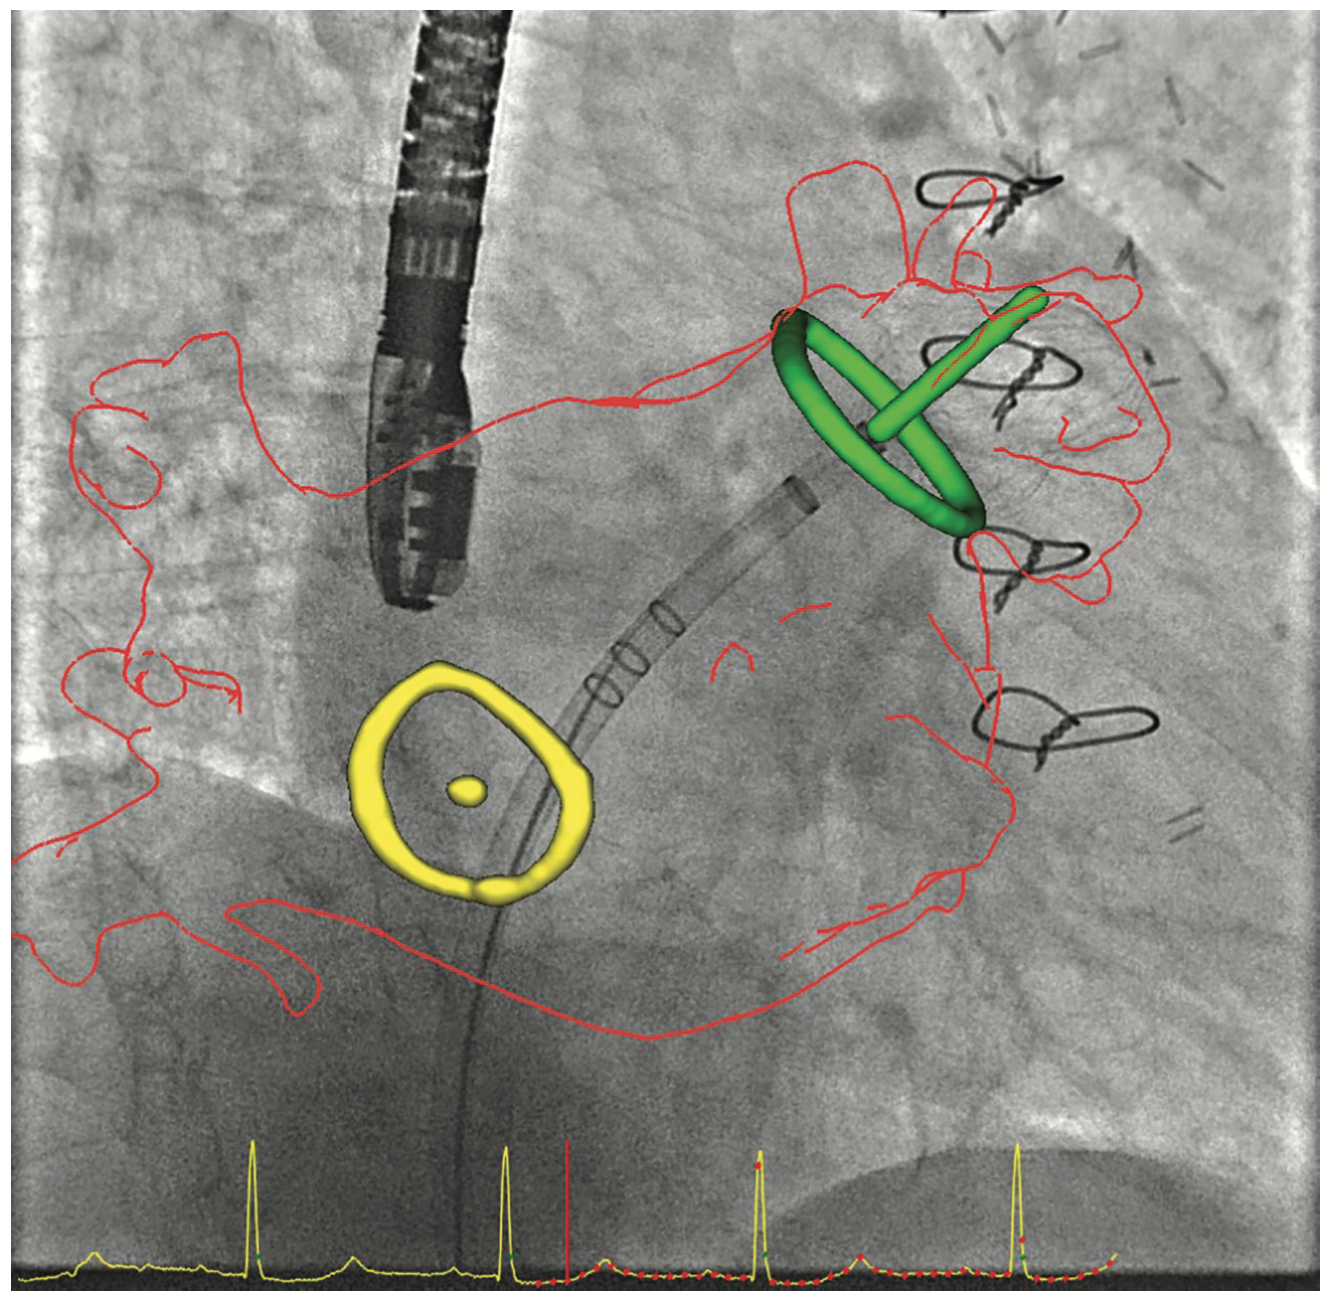

GE HealthCare’s fusion system helps by allowing us to fuse the live fluoroscopy to the pre-procedure CT scan. Most of the time, before walking into the room for a TAVR, for example, you already will have a fairly good understanding of how valve alignment is going to take place, because of the pre-procedure imaging. Fusion technology plus additional software that we use allows us to determine the angulation and directs how to position our detector so we have the best views for performing TAVR. The fusion software also allows us to further minimize the dose of radiation during the procedure, particularly in complex procedures, using distal protection such as the Sentinel™ system to protect the cerebral circulation in patients who are undergoing TAVR.

Praveen Mehrotra, MD: There are several echocardiographic technologies, recently developed, that help to solve some of the imaging challenges during structural heart procedures. First and foremost is the need for outstanding 3D volumetric and multiplanar imaging with high spatial resolution and frame rates. We use live 3D imaging to help guide certain procedures and to obtain critical measurements prior to the start of the procedure, usually for device sizing. There is a new technology called 4D Markers (GE HealthCare), which we can place on 2D and 3D echo images. The interventional cardiologist can view the 4D Markers onscreen and use them as a target, so he or she knows where we are asking them to direct a wire or catheter without the echocardiologist having to verbalize it or struggle to communicate that information. The markers exist in 3D space, so we can see them in multiple views simultaneously. Another useful technology called View-X (GE HealthCare) places the fluoroscopic image adjacent to the TEE image on the echo machine. This technology allows me to visualize the procedure from the standpoint of the interventionalist, integrate fluoroscopic and echocardiographic data, and anticipate what information will be needed next by the interventional cardiologist or surgeon.

We are also starting to use fusion technology. There are several different types of fusion imaging technology currently available on the market; one recently released fusion technology is CT-Echo Fusion (GE HealthCare) that fuses previously acquired CT data to the live 3D echo image. Echocardiography can suffer due to dropout from calcification or devices. This fusion technology allows us to integrate CT imaging that we already utilize for pre-procedural planning of structural heart procedures and integrate that with the echocardiographic images obtained on the day of the procedure. These fusion technologies are currently evolving and may prove to be very useful in complex structural heart procedures where echocardiography alone may not be sufficient.